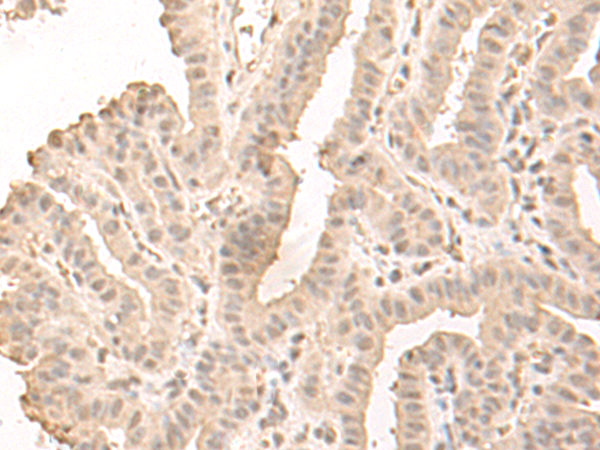

IHC positive control: |

Human esophagus cancer |

IHC Recommend dilution: |

30-150 |